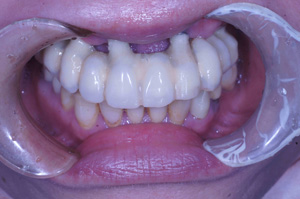

@@R.S‚³‚ñ@56Î —«  ‘åŠw‹³Žö @Žèp“ú@‚Q‚O‚O‚W”N ‚QŒŽ ‚X“úi“yj@㉺Š{  ƒm[ƒxƒ‹ƒKƒCƒhŽg—p@Ö¬“à’ÁÖ@•¹—p@@@

@@@@@ãŠ{  All on ‚U@‘¦Žž‰Ád@@

@@@@@@@@@@@@@ Rpl Tapered Rp  ‚P‚O mm(‚U–{)

@@@@@‰ºŠ{¶‰E@‘¦Žž‰Ád@ ‚R Unit Bridge@

@@@@@@@@@@@ @Rpl Tapered Rp  ‚P‚O mm(‚S–{)@@–ƒWƒ‹ƒRƒjƒAƒNƒ‰ƒEƒ“‚ÅÅI•â’Ô